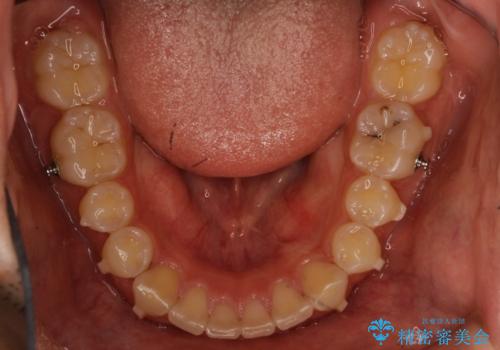

- 出っ歯を主訴に来院されました。

上の歯が全体的に下の歯の位置に比べると前方に位置しており、上の前歯が前方に傾斜している状態でした。

治療途中に転勤されて、簡単にはお越し頂けなくなり、来院頻度が少なくなってしまいましたが、しっかり使っていただけたことで計画通り歯を動かすことができました。